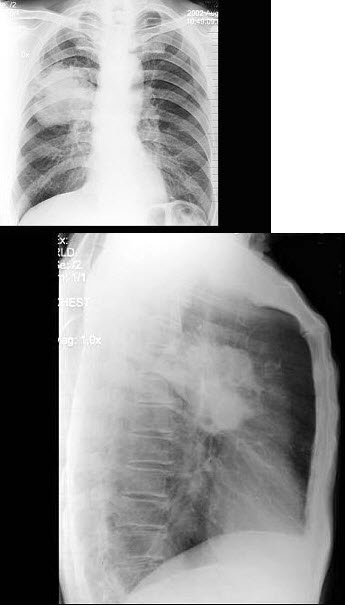

48、单项选择题

女,31岁,咳嗽发热1周,胸片检查如图,最可能的诊断是()

A.两肺结核

B.两肺炎症

C.两侧胸膜炎

D.两肺不张

E.慢性支气管炎